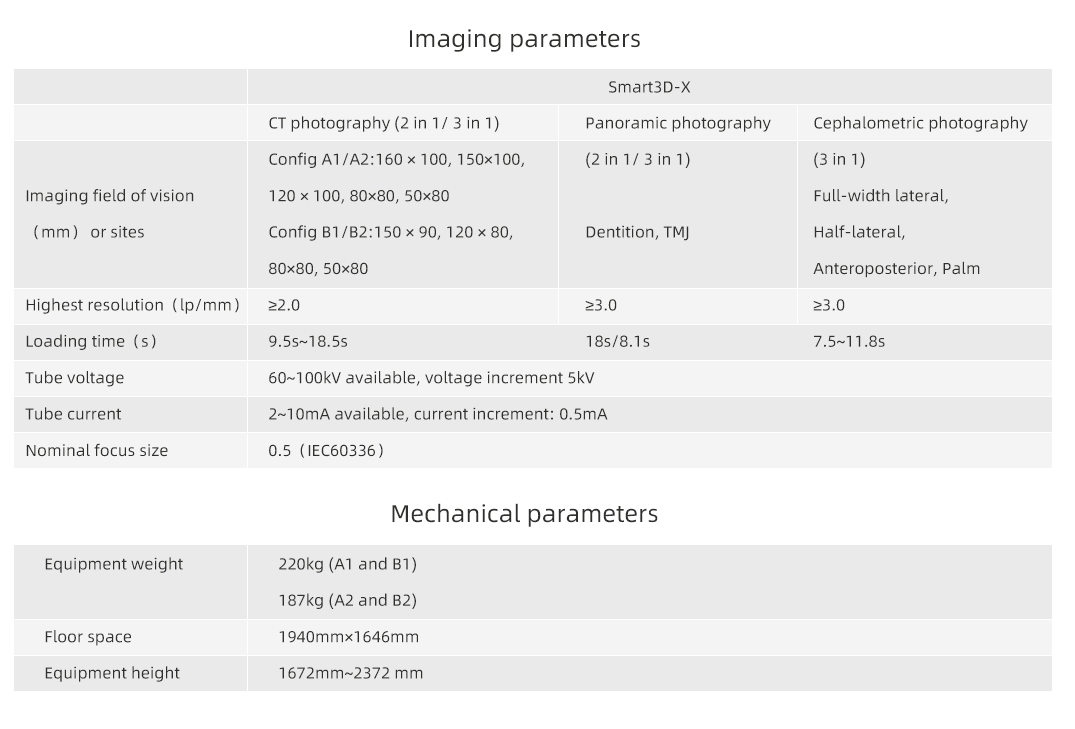

The system achieves image resolutions up to 2.0 lp/mm with a voxel size range of 0.05 – 0.25 mm.

Its 0.5 mm small focus tube guarantees smooth, stable, and reliable scans.

Resolution up to 2.0lp/mm, voxel size of 0.25~0.05 mm optional.

Product Size Display of LargeV Dental CBCT Machine

Designed for space efficiency and comfort. Every detail supports easy operation and clear imaging results.